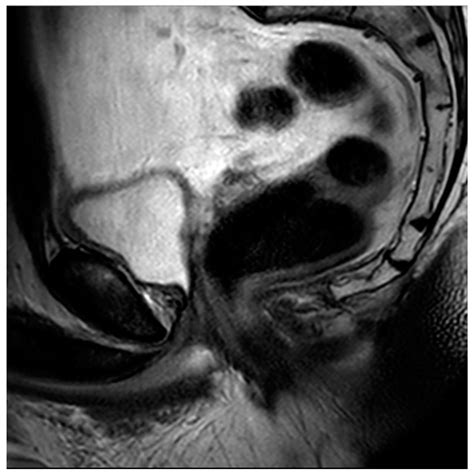

An MRI of prostate is a magnetic resonance imaging scan that uses powerful magnets and radio waves to create detailed images of the prostate gland. Unlike other imaging techniques such as ultrasound or CT scans, MRI provides high-resolution images that can detect even small abnormalities within the prostate. This makes it an invaluable tool for diagnosing and staging prostate cancer, as well as monitoring the effectiveness of treatments.

• Multiparametric MRI (mpMRI): This technique combines multiple MRI sequences, including T2-weighted imaging, diffusion-weighted imaging (DWI), and dynamic contrast-enhanced (DCE) imaging, to provide a comprehensive evaluation of the prostate.

• Prostate Imaging Reporting and Data System (PI-RADS): This standardized reporting system helps radiologists interpret MRI findings and classify the likelihood of clinically significant prostate cancer.